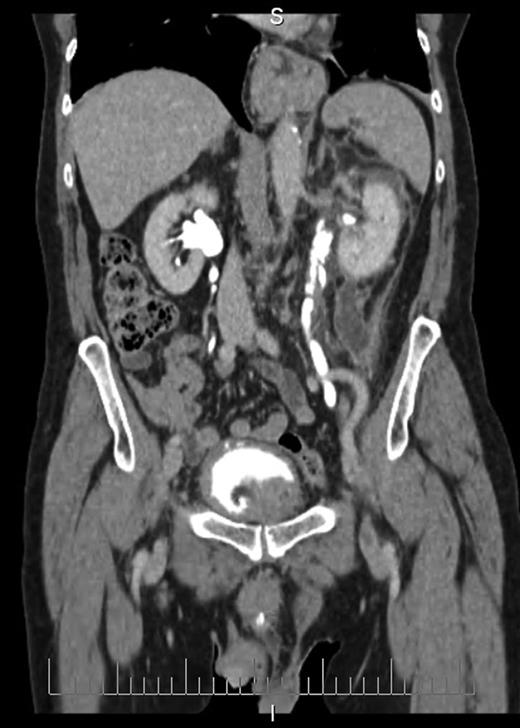

Coronal section CT image demonstrating fluid collection extending down left paracolic gutter. Also visible are massively enlarged prostate and urinary extravasation from left ureter.